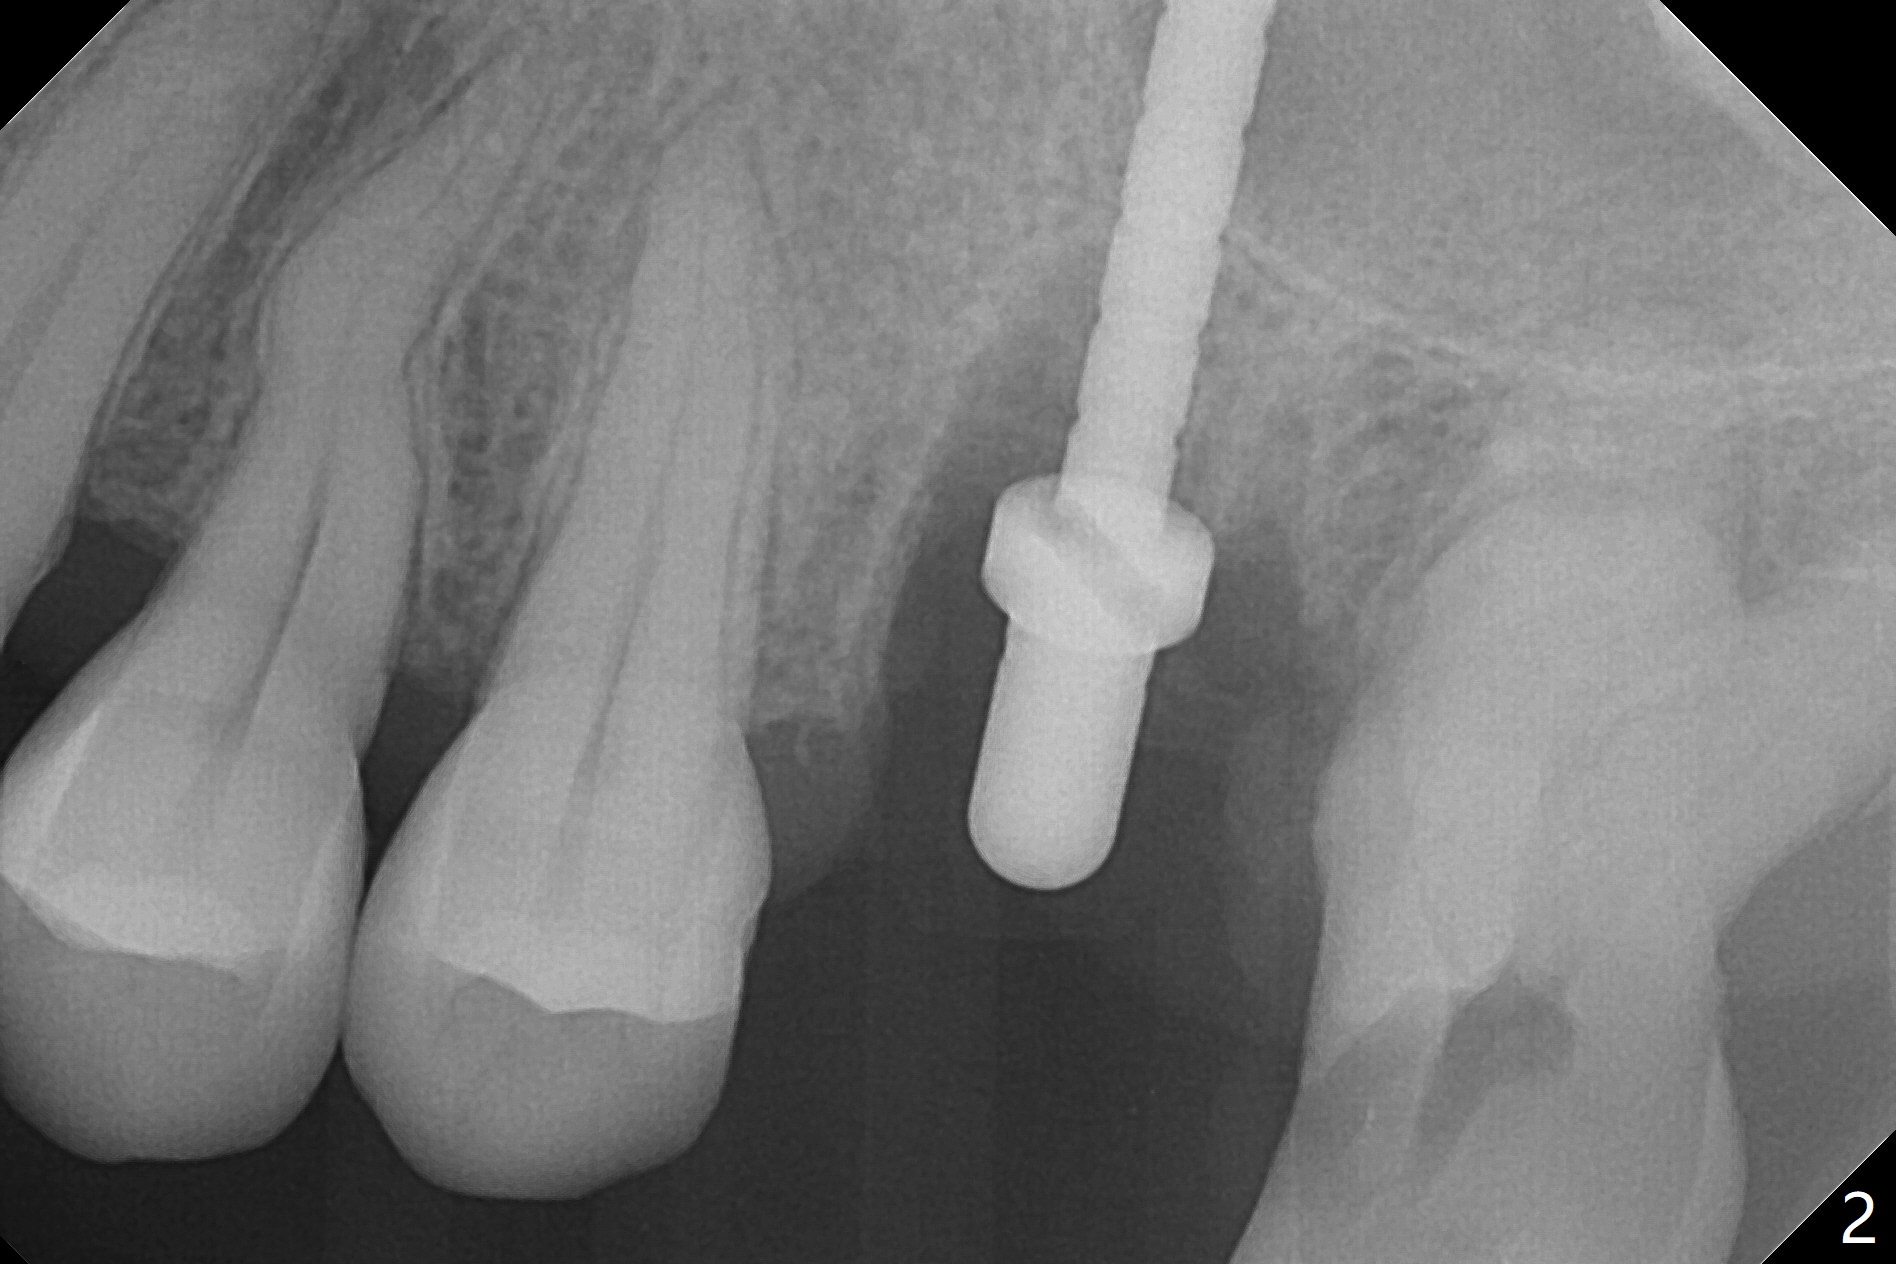

8.5 mm Osteotomy in Septum

After removal of granulation tissue from the sockets associated with the fractured tooth at #14 (Fig.1 (* granulation tissue)) and initial osteotomy in the septum with a 2 mm drill for 8.5 mm, the sinus floor is penetrated by a parallel pin (Fig.2). But the sinus membrane remains intact until osteotomy finishes with a 4.8 mm drill. Following sinus lift with Vera Graft with autogenous bone (Fig.3 red *), a 5.5x10 mm implant is placed ~ 1 mm coronal to the septal crest and 1-3 mm apical to the surrounding crest (mesiodisto-buccopalatal, >55 Ncm). After further bone graft around the implant (Fig.3 white *), a 6.5x4(3) mm abutment is inserted with the 3rd round of grafting (Fig.3,4 black *). An immediate provisional is fabricated to keep the allograft in place. The implant seems to have osteointegrated 5 months postop (Fig.5).